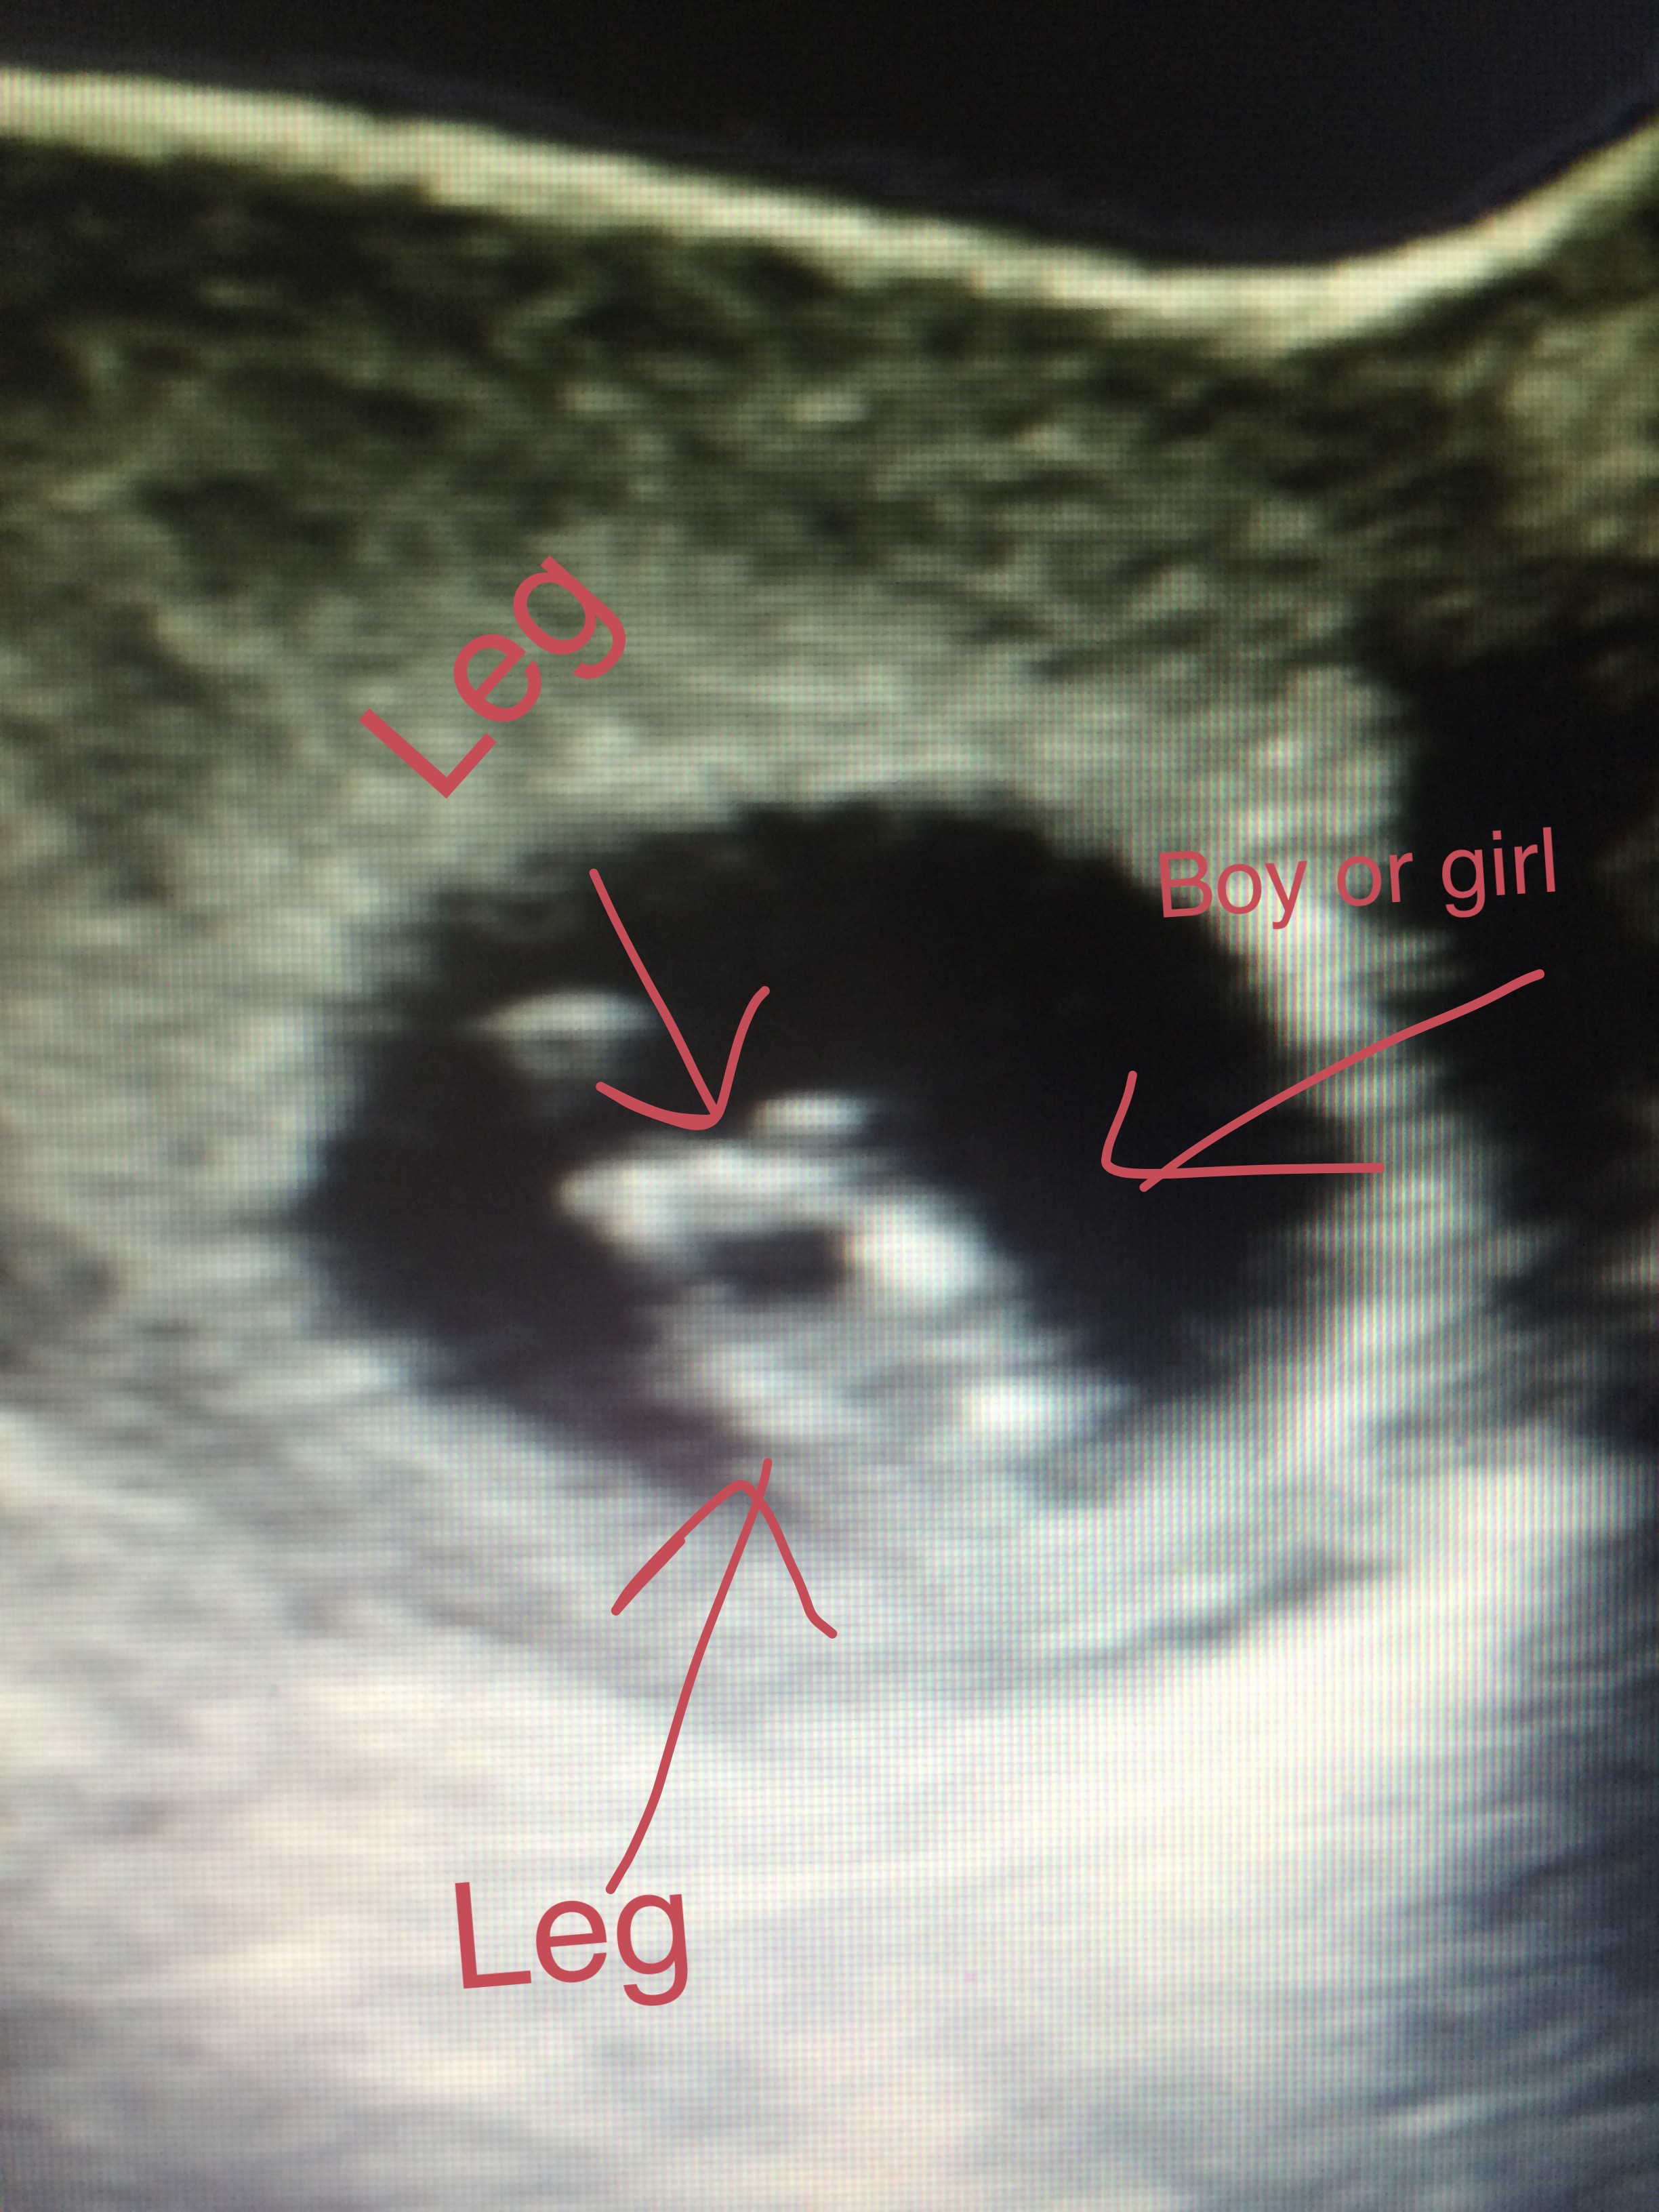

I know it is to early for the potty shot, but I'm just looking for people's guessesAttachment 27900

Image is just hard to decipher.

This image is so tough. But really, even if it was clear, at 12 weeks you would see a protrusion for both boy and girl. So, potty shots are really only good many weeks after 12. Sorry! 50/50 on this one.

Both boys n girls have a bulge potty shot unreliable